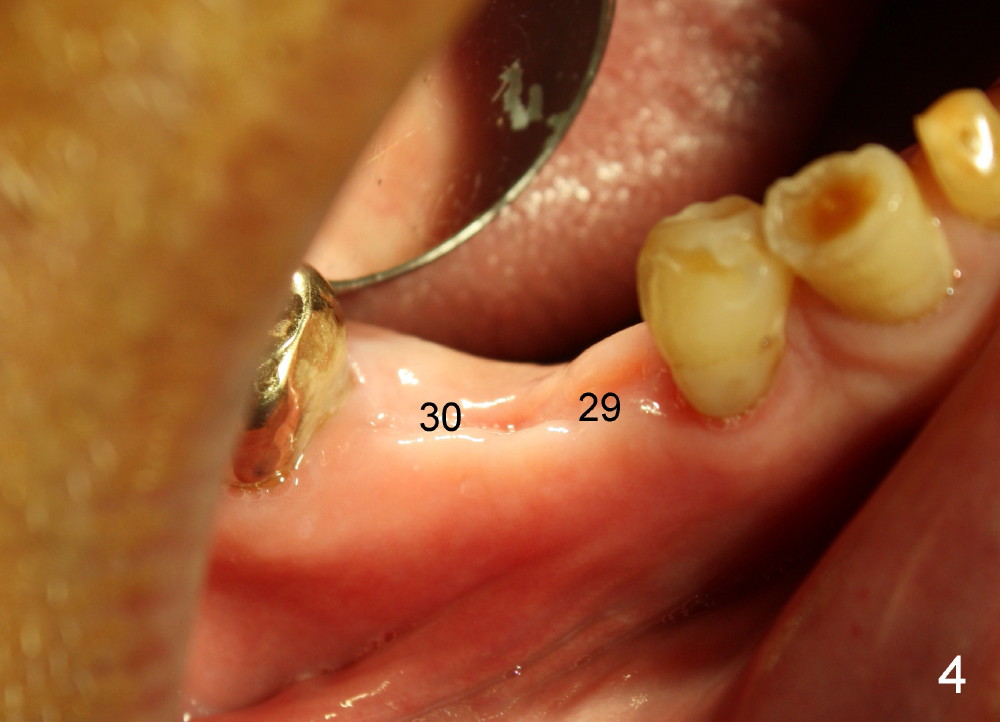

Three months later, the B-L width at the site of #29 is significantly reduced (Fig.4). Upon X-ray exam, there is decreased bone density between these two sockets (Fig.5 *). Socket preservation seems not to live its expectation. The obvious advantage is formation of callus-like bone in the molar socket (Fig.6 *, between the buccal (B) and lingual (L) plates). The significant decrease in the buccolingual width at the site of #29 is associated with buccal plate crack during implantation (Fig.7 *). At the site of #30, the lingual plate is so low that there is implant thread exposure (Fig.8 <). Mixture of autogenous bone (harvested from drilling with Bicon reamers) and synthetic bone (Osteogen) is placed mainly buccal to the implant #29 and lingual to #30 (Fig.9), followed by collagen membrane. Bone density between these two implant increases due to the bone grafting (Fig.10 *, as compared to Fig.5). In fact, the implant at the site of #29 is found loose 1 month postop.